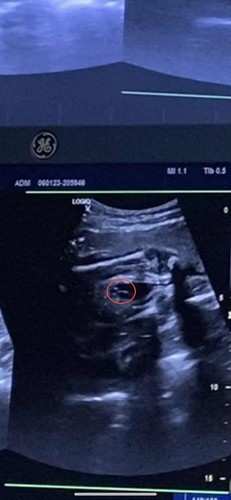

แม่ๆแนะนำวิธีคลายความกังวลหน่อยค่ะ ช่วงนี้กังวลมากกลัวลูกขาดโฟลิกกลัวลูกเกิดมาพิการ ร่างกายไม่แข็งแรง กลัวเกิดมามีโรคประจำตัว แต่เราก็บำรุงนะคะอาหารการกินสลับเมนูไปมา แต่ตอนเช้าดื่มแค่นม1กล่องขนมปัง1แผ่น มีของยิบย่อยบ้างตอนเวลาทำงาน กินโฟลิกวันละ1เม็ด เพิ่มนมและไข่วันละ1-2ฟองและผลไม้ พยายามทานอาหารให้ครบ5หมู่ เราฝากครรภ์ตั้งแต่ตรวจเจอ2ขีด ไปซาวด์ครั้งแรกยังไม่เจอถุงตั้งครรภ์เลย แต่ก็ยังกลัวอยู่ดีทำไงดีคะแม่ๆ มีใครบำรุงแต่ลูกออกมาไม่แข็งแรงบ้างไหมคะ#ขอบคุณล่วงหน้านะคะ #คุณแม่ๆช่วยแนะนำหน่อยค่ะ